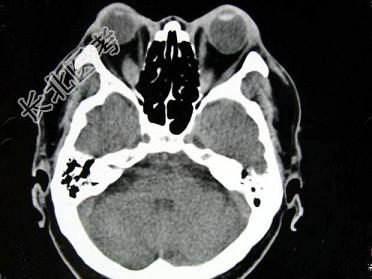

- 单项选择题女,50岁, 消瘦、多饮多食,脖子粗大, 双侧眼球突出1年余,CT检查如图所示, 应考虑为 ( )

A、眼型格氏病

B、甲状腺眼病

C、炎性假瘤

D、横纹肌肉瘤

E、眶部结核